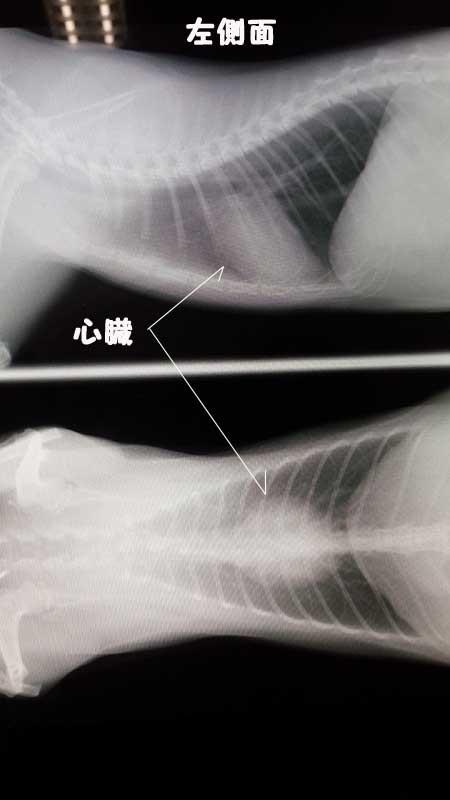

これが先日撮影したものです。

半年前と比べると体格も心臓も大きく成長してます。

左側にかすかに針のようなモノが見えますがICチップだそうです。